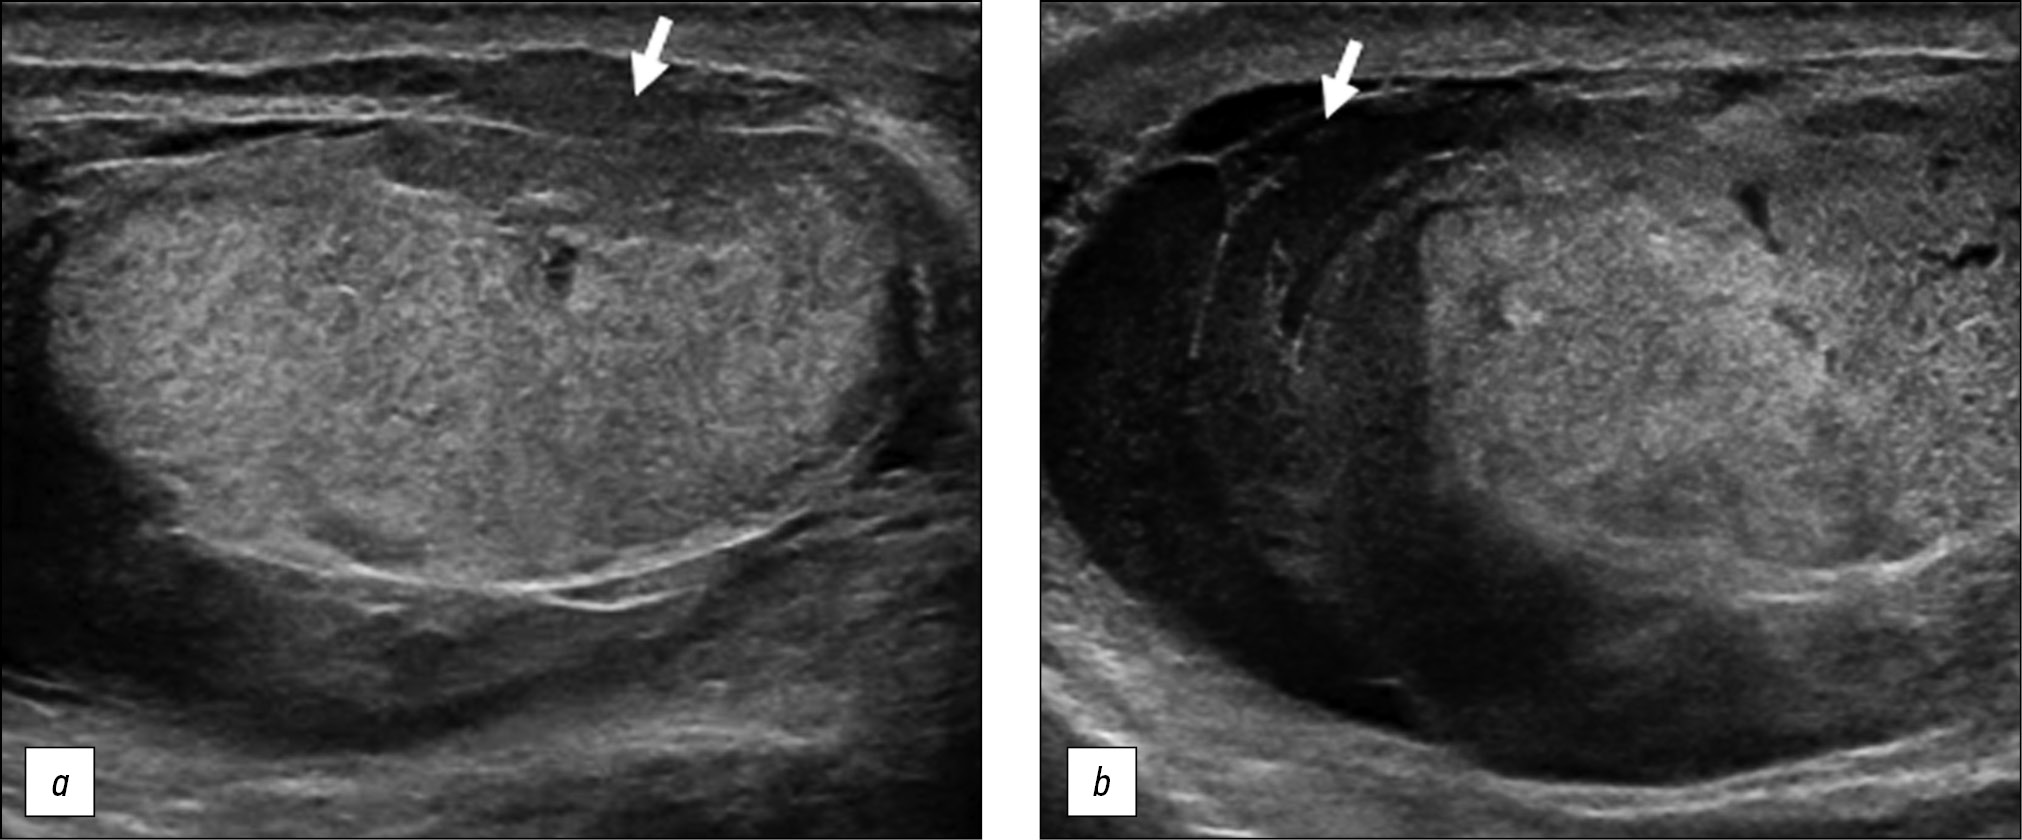

A healthy 15-year-old male teen was hit in the scrotum with a kick in the groin during a football match. He had an immediate and severe pain. After a few hours, although symptoms had improved, he presented to our emergency department with persistent swelling and purplish discoloration of the left scrotum. He did not report any other injuries. The genitourinary examination revealed that the left hemiscrotum was about two times larger than the right with severe ecchymosis. The left testicle was difficult to palpate because of pain and swelling, whereas the right testicle had a normal size and did not reveal any palpable abnormalities. The cremasteric reflex was not elicited on the left side. Scrotal ultrasonography (US) showed moderate scrotal edema and hematocele with a discontinuity in the tunica albuginea characterized by an abnormal contour (Figure 1). Color Doppler US (CDUS) documented a loss of vascularization in the upper pole that extruded into the broken portion of the testicle of approximately 2.5 cm (Figure 2) but no evidence of torsion or infarction. Urology consultation was requested, and a contrast-enhanced US (CEUS) was performed, which confirmed the diagnosis of testicular rupture and determined the amount of the vital parenchyma (Figure 3). The patient was hospitalized for urgent examination of the left hemiscotum based on the US results. During surgery, a large hematocele was evacuated, and a closer inspection of the testicle revealed a lesion of the tunica albuginea. Primary closure of the tunica was performed (Figure 4). The patient made an uneventful recovery, and he was discharged after 4 days.

Figure 1. B-mode ultrasonography images. (a) Interruption of the tunica albuginea with the protrusion of echogenic material (arrow) that represents an index of breaking. (b) Hematocele of moderate size (arrow) and a heterogeneous appearance of testicular parenchyma, attributable to an intratesticular contusion.

Figure 2. Color Doppler ultrasonography image showing an irregular testicular morphology with an avascular area at the breaking point (arrow).